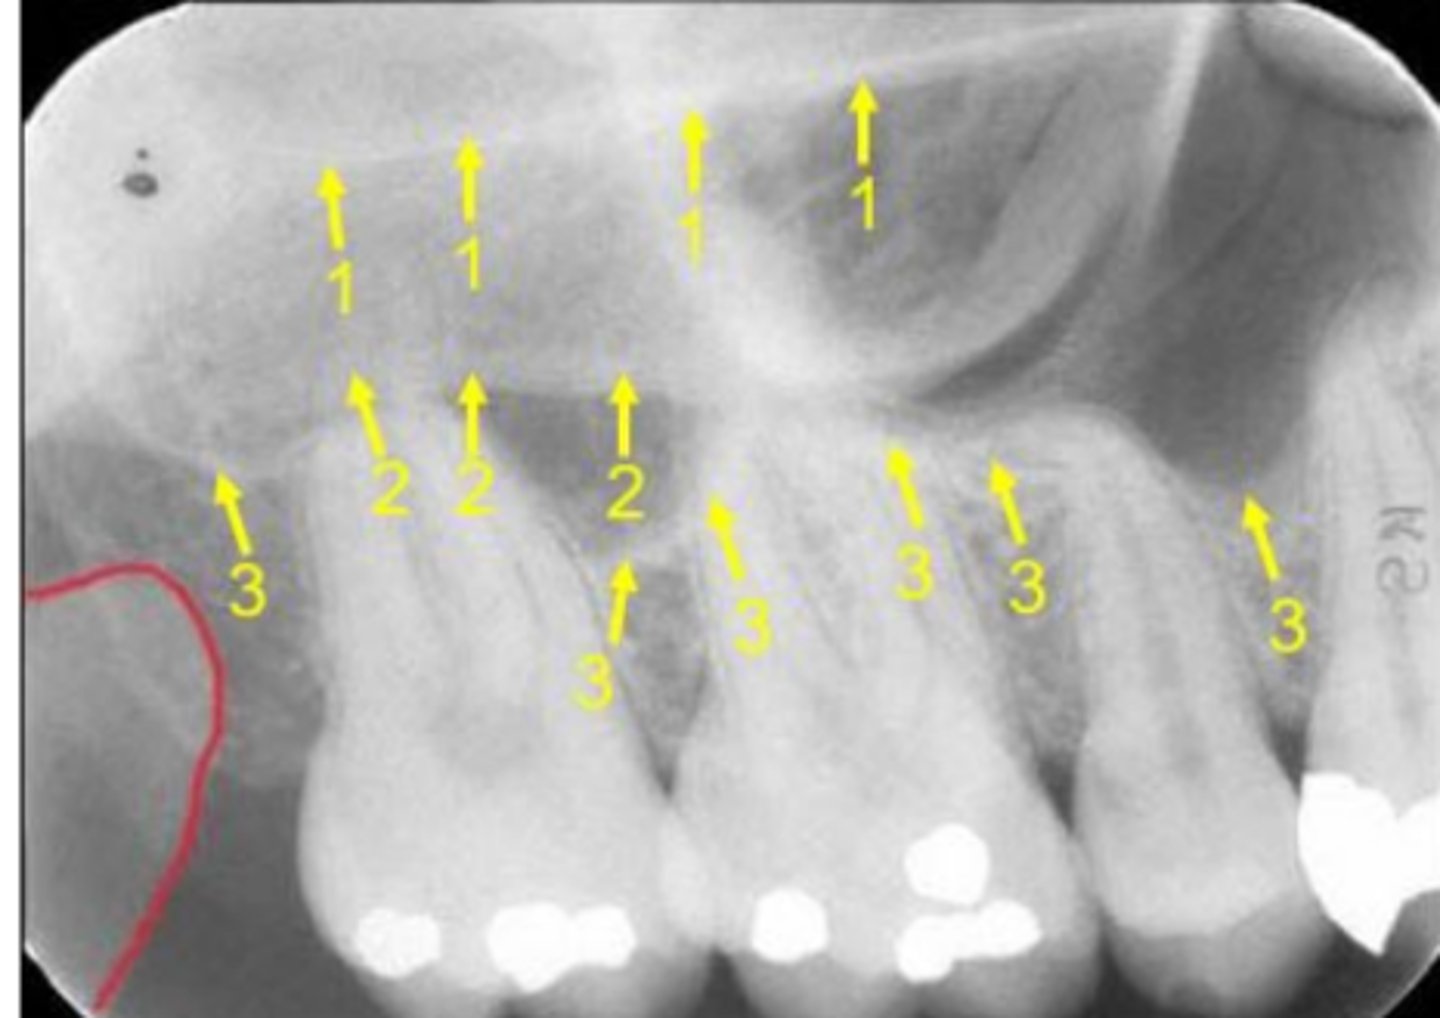

Floor of maxillary sinus

Name the curved, radiopaque line that superimposes the roots of the teeth indicated by #7.

Floor of the maxillary sinus

Name the line indicated by arrows labeled #2.

Hamulus

Name the elongated radiopacity indicated by #5.

Lateral pterygoid plate

Name the large radiopacity with a rounded inferior margin indicated by #4.

Zygoma

Name the horizontal radiopaque line labeled #2.

Name the curved line scalloping between tooth roots labeled #3.

Coronoid process

Name the curved, conical structure outlined in the bottom left corner of the image.

Ala of the nose

Name the curved, radiopaque structure indicated by arrow #3.

Name the curved, hyperdense line that superimposes the roots of the teeth indicated by #7.

Floor of the nasal cavity

Name the line indicated by arrows labeled #1.

Inverted Y

Name the two thin, curved, radiopaque lines that merge indicated by arrows #4.